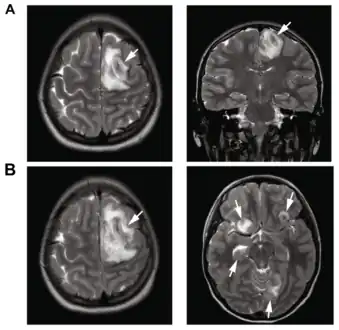

Image of granulomatous amoebic encephalitis caused by Acanthamoeba -

A: T2-weighted MRI showing liquefied, necrotic brain tissue as a result of GAE caused by Balamuthia mandrillaris

B: T1-weighted MRI showing expansion and addition of necrotic areas 4 days later